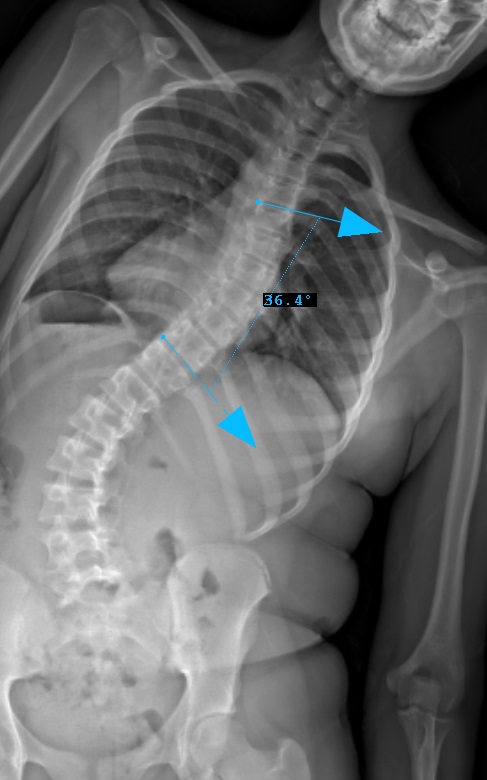

Preop: 1C- Examples

Preop RIGHT Bend

Curve Type 1

Thoracic curve major, other curves non-structural (bend out to <25o)

Lumbar modifier C

CSVL does not touch apex of lumbar curve

(apex - L1/2 disc)

Therefore, Classification is Type 1C-